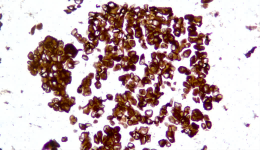

| Description | CLDN18.2是Claudin蛋白質(zhì)家族的一員,位于細(xì)胞膜表面,Claudin18.2(CLDN18.2)表達(dá)具有特異性。其作為Claudins蛋白的一個(gè)亞型,在正常組織中僅表達(dá)于分化的胃黏膜上皮細(xì)胞。在胃癌、食管癌和胰腺癌等多種腫瘤中表達(dá),并且不僅限于原發(fā)病灶,在轉(zhuǎn)移灶中也有表達(dá)。目前臨床研究中使用的檢測方法均為免疫組化。 |

| 示例 | ![]() |

| IHC染色結(jié)果 | |